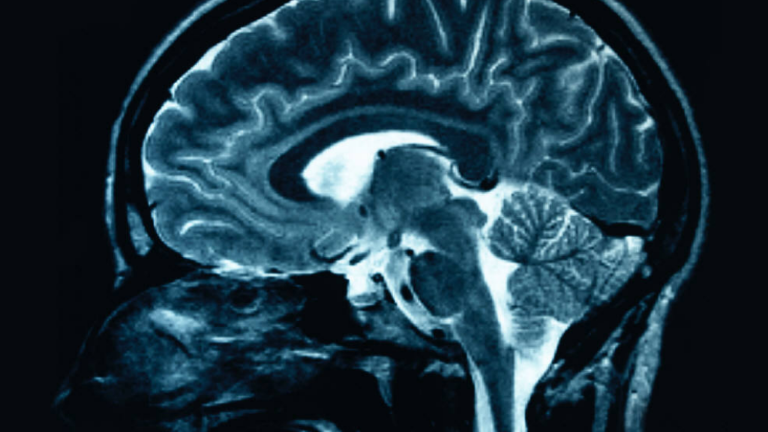

Los Angeles.- Un estudiante californiano se quejaba de violentas migrañas y los médicos finalmente hallaron al culpable: una lombriz solitaria que se había alojado en su cerebro... y casi le cuesta la vida.

Radiografías de su cerebro revelaron así la presencia del intruso, que se había instalado en un quiste.

"¡Oh! Tiene un parásito en su cabeza. Vamos a operarlo y rápido, porque si no probablemente morirá", recordó que le dijeron los médicos.

Cómo la lombriz solitaria, que en general opta por alojarse en el intestino, llegó a ese lugar, aún es un misterio tanto para los médicos como para Ortiz, que ahora manifiesta estar "feliz de estar vivo".